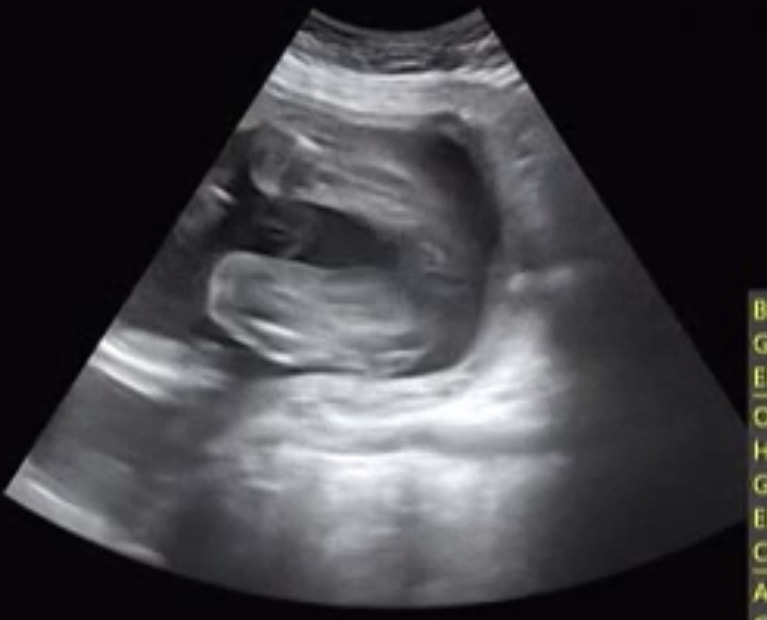

KakaoTalk_20190721_113131176.jpg 있을 만큼 있었다고!!(재하의 귀여운 다리)